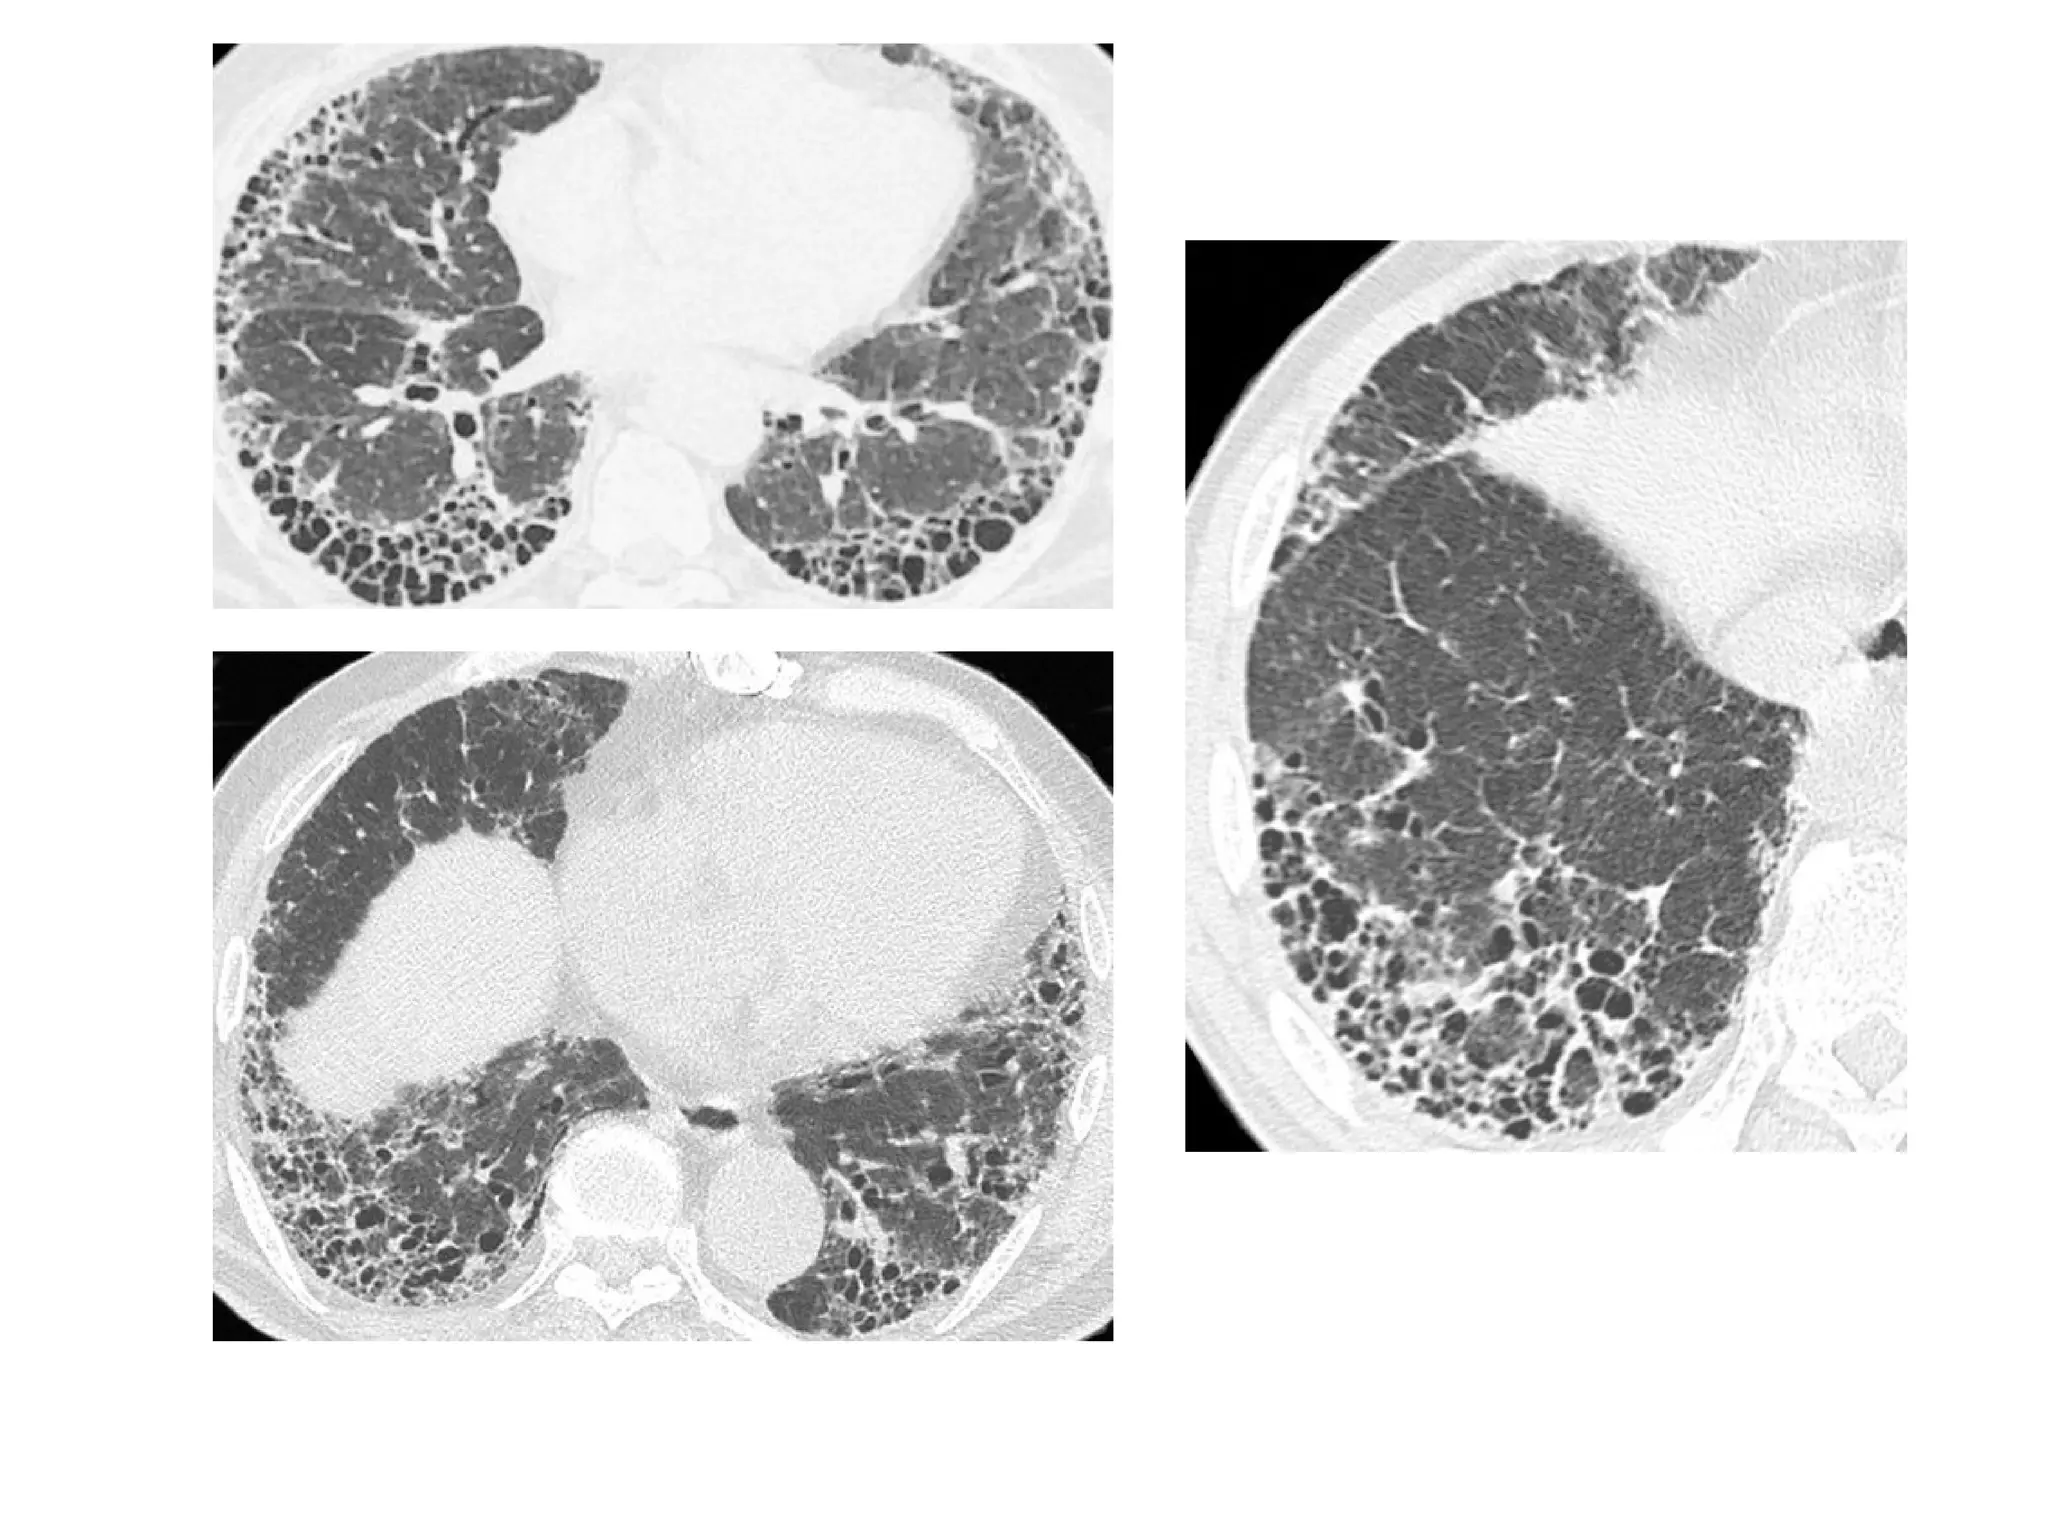

Honeycombing

• It represents the second type of reticular opacity

• Fleischner Society definition

• “On CT scans, the appearance is clustered cystic air spaces, typically

of comparable diameters on the order of 3–10 mm but occasionally

as large as 2.5 cm. Honeycombing is usually subpleural and is

characterized by well-defined walls. It is a CT feature of established

pulmonary fibrosis and is an important criterion in the diagnosis of

usual interstitial pneumonia.”